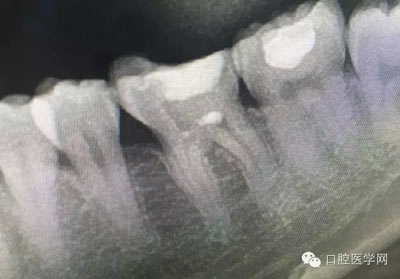

幾例根管再治療病例

這是一例外院樹脂修復后十個月出現(xiàn)牙髓炎癥狀的患者。遇到這樣子的患者大家會怎么做,證明選擇,還有就是可做可不做治療的如何去平衡。